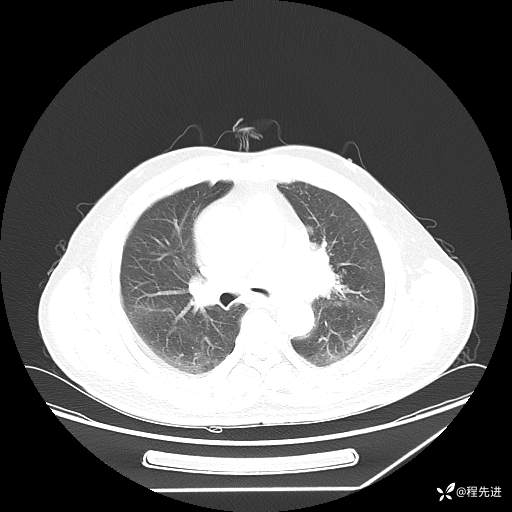

患者性别:男

患者年龄:57岁

简要病史:声嘶2月余

CT平扫+增强: